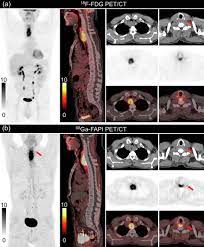

Pet Scan Cpt Code 2020 : The scan shows if there is any tumor or blockage by highlighting the part of organ.. All pet scan services require the use of a radiopharmaceutical diagnostic imaging agent (tracer). Jun 09, 2020 · code description. Myocardial imaging, positron emission tomography. (5 days ago) jan 28, 2020 · cpt code for pet scan of lungs. Nov 09, 2017 · normal and abnormal tissues.

The scan shows if there is any tumor or blockage by highlighting the part of organ. Each of these cpt codes always requires the use of a radiopharmaceutical code, also known as a tracer code. For pet scan of lungs, radioactive tracer element fluorine is injected inside the body and let is absorb by the lungs. Based on the axumin prescribing information, it is expected that the following two cpt codes will be commonly used for axumin pet or pet/ct imaging of patients with recurrent prostate cancer: Mm11537 related cr release date: All pet scan services are billed using pet or pet/ computed tomography (ct) current procedural terminology (cpt) codes 78459, 78491, 78492, 78608, and 78811 through 78816. What is the cpt code for pet? The cpt code for this procedure is 78814. Nov 09, 2017 · normal and abnormal tissues. The applicable tracer code should be billed when billing for a pet scan service. All pet scan services require the use of a radiopharmaceutical diagnostic imaging agent (tracer). Related change request (cr) number: The images on computer are clear because of dye injected.